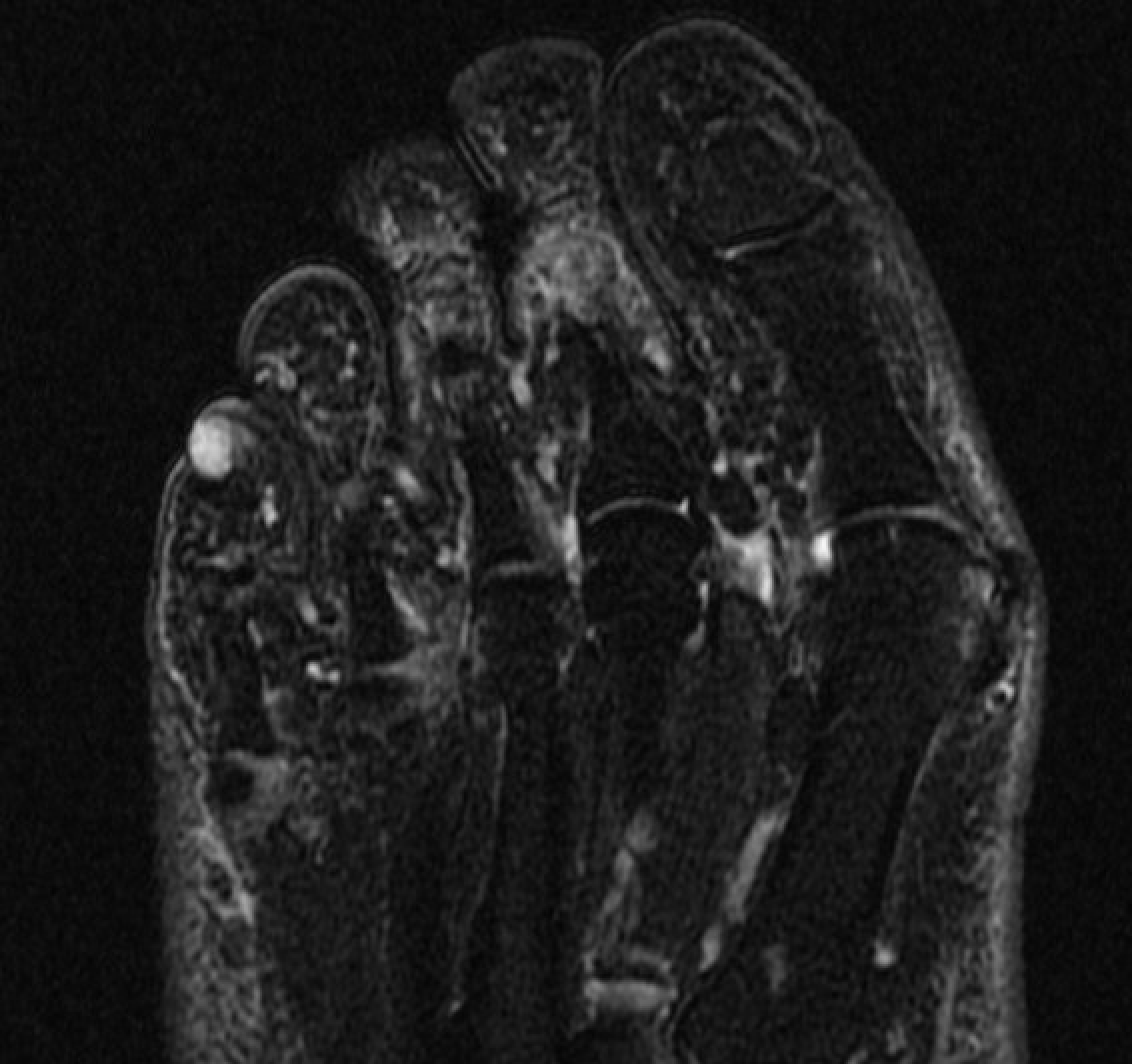

GCT flexor tendon sheath

GCT of tibialis posterior tendon sheath